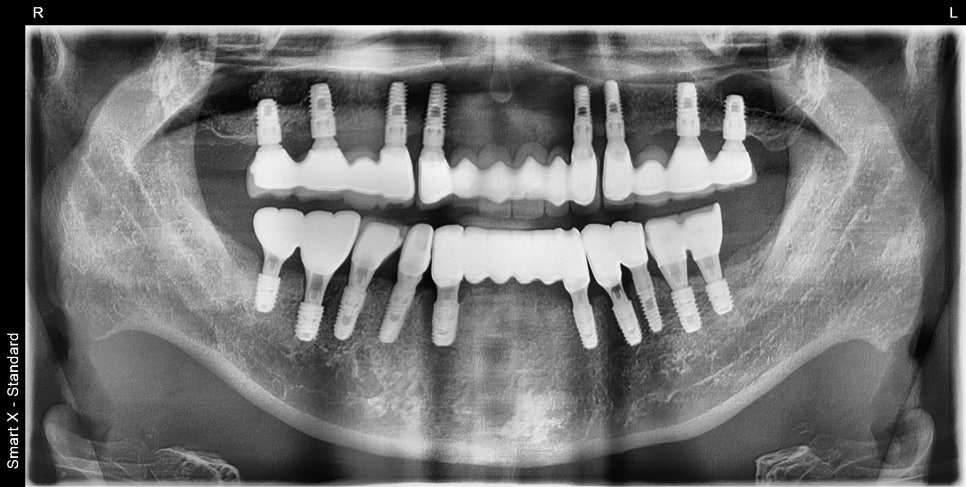

치료 후: 최종 보철물 완성 후 엑스레이, 정면·측면 사진

치료가 완료된 후 파노라마 엑스레이입니다. 임플란트가 안정적으로 유착되었고 교합도 잘 맞는 상태입니다.